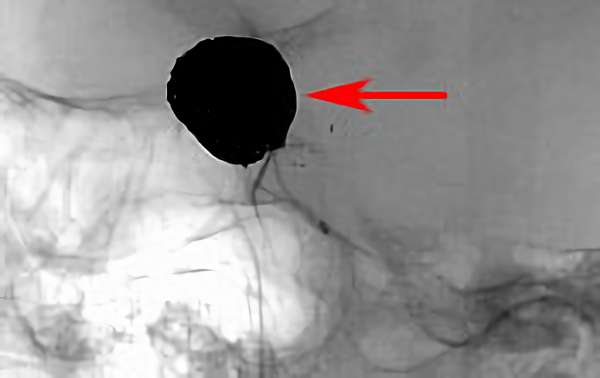

'26年4月

左後下小脳動脈瘤

80代

大阪府の病院

No.1631 手術前

No.1631 手術中

No.1631 手術後